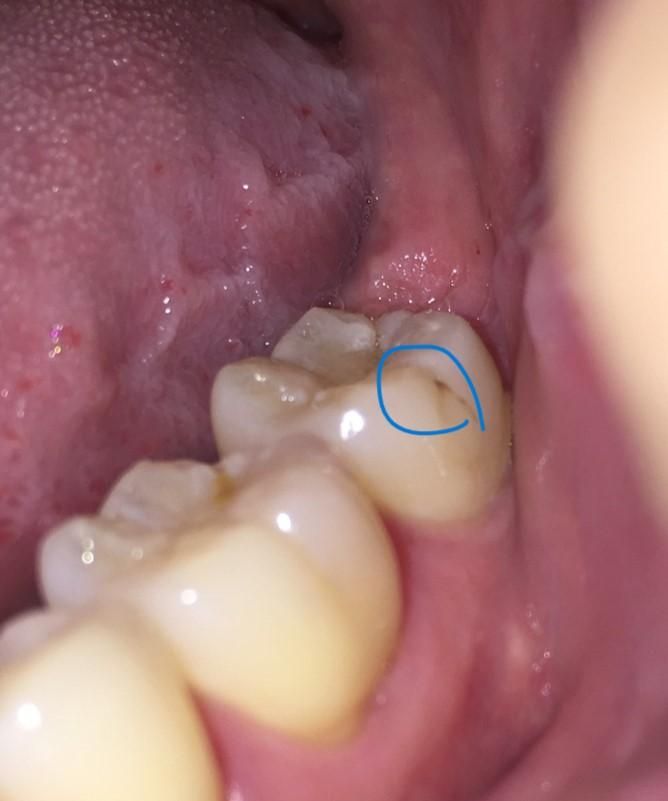

어금니 금? 혹은 충치 또는 현재 어떤 상황인지 궁금합니다.

왼쪽 어금니이구요

우연히 발견했는데 양치 한 상태이고 치석제거기 끌로 긁어봐도 안 지워지는듯 합니다.

한번씩 양치하다 어금니를 닦을때 특정 자세?에서 좀 시릴때? 아릴때가 있는데

혹여 금이 갔다거나 아니면 충치인지 궁금합니다.

치아옆면에 충치 있는 것 확실합니다. 가능한 빨리 치과에 가서 충치치료 해야 할 것으로 보입니다. 실금이 간 것은 아닙니다.

금이간건 아니고 예전에 레진으로 치료를 한곳이 시간이 지나면서 틈이 생기면서 착색이 된 상태 같습니다.

사진으로 봤을 경우에는 충치일 수도 있지만 착색일 수도 있습니다.

또한 금이 간 부분에 치아가 착색이 된 부분이 있을 수도 있습니다. 치아에 금이 갔을 경우에는 보철 치료 등으로 치아를 보호해 줘야 하며 단순 충치였을 경우에는 충치 치료가 필요할 수 있습니다

사진으로만 보기에는 금이 가거나 충치가 생긴 것은 아니고 기존 레진 수복물 주위로 변색 및 착색이 발생한 것으로 보입니다. 다만 간혹 칫솔질 하실 때 그런 느낌이 드는 것은 충치나 금 때문이라기 보다는 치경부 마모증 때문일 가능성이 높고 금이 있는 경우에는 식사 시에 갑자기 찌릿한 통증이 깜짝 놀랄 정도로 찾아오기 때문에 큰 걱정은 하지 않으셔도 되겠습니다.

이전에 떼운 재료의 변색인 듯 하지만 증상이 있다면 엑스레이 찍어보고 이차충치를 확인해봐야 합니다